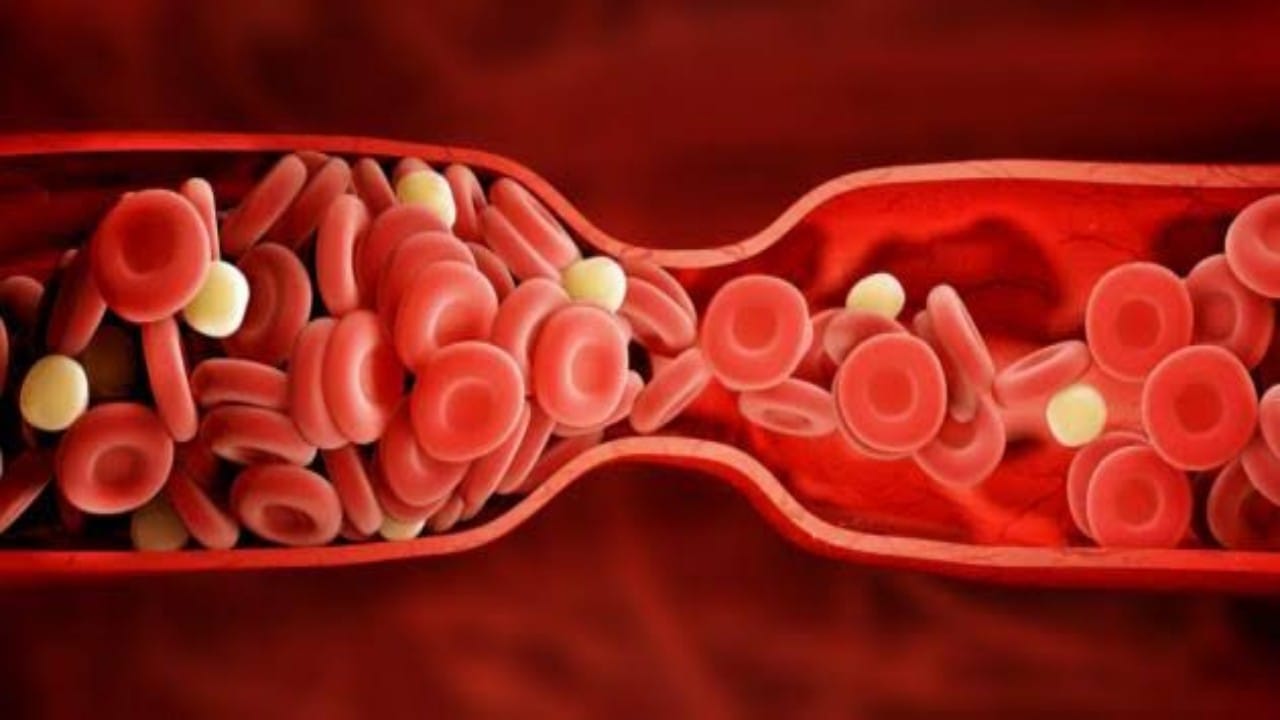

الجلطات

استشاري : الكوليسترول النافع يقي من الجلطات .. فيديو

استشاري يكشف سبب كثرة الجلطات في فصل الشتاء..فيديو

علامات مبكرة للجلطات الدماغية

طبيب يكشف عن 5 طرق لتقليل أعداد الجلطات في المملكة

النمر يوضح علاقة الكدمات الشائعة في النساء بالجلطات

خالد النمر: المرأة بعد انقطاع الطمث تكون عرضة للإصابة بالجلطات

“أخصائي” يوضح لماذا تكثر الجلطات في فصل الشتاء (فيديو)

بالفيديو.. “النمر” يكشف السبب وراء كثرة الجلطات في الصباح الباكر

“النمر” يوضح مدى خطورة المشي حافي القدمين وعلاقته بالجلطة